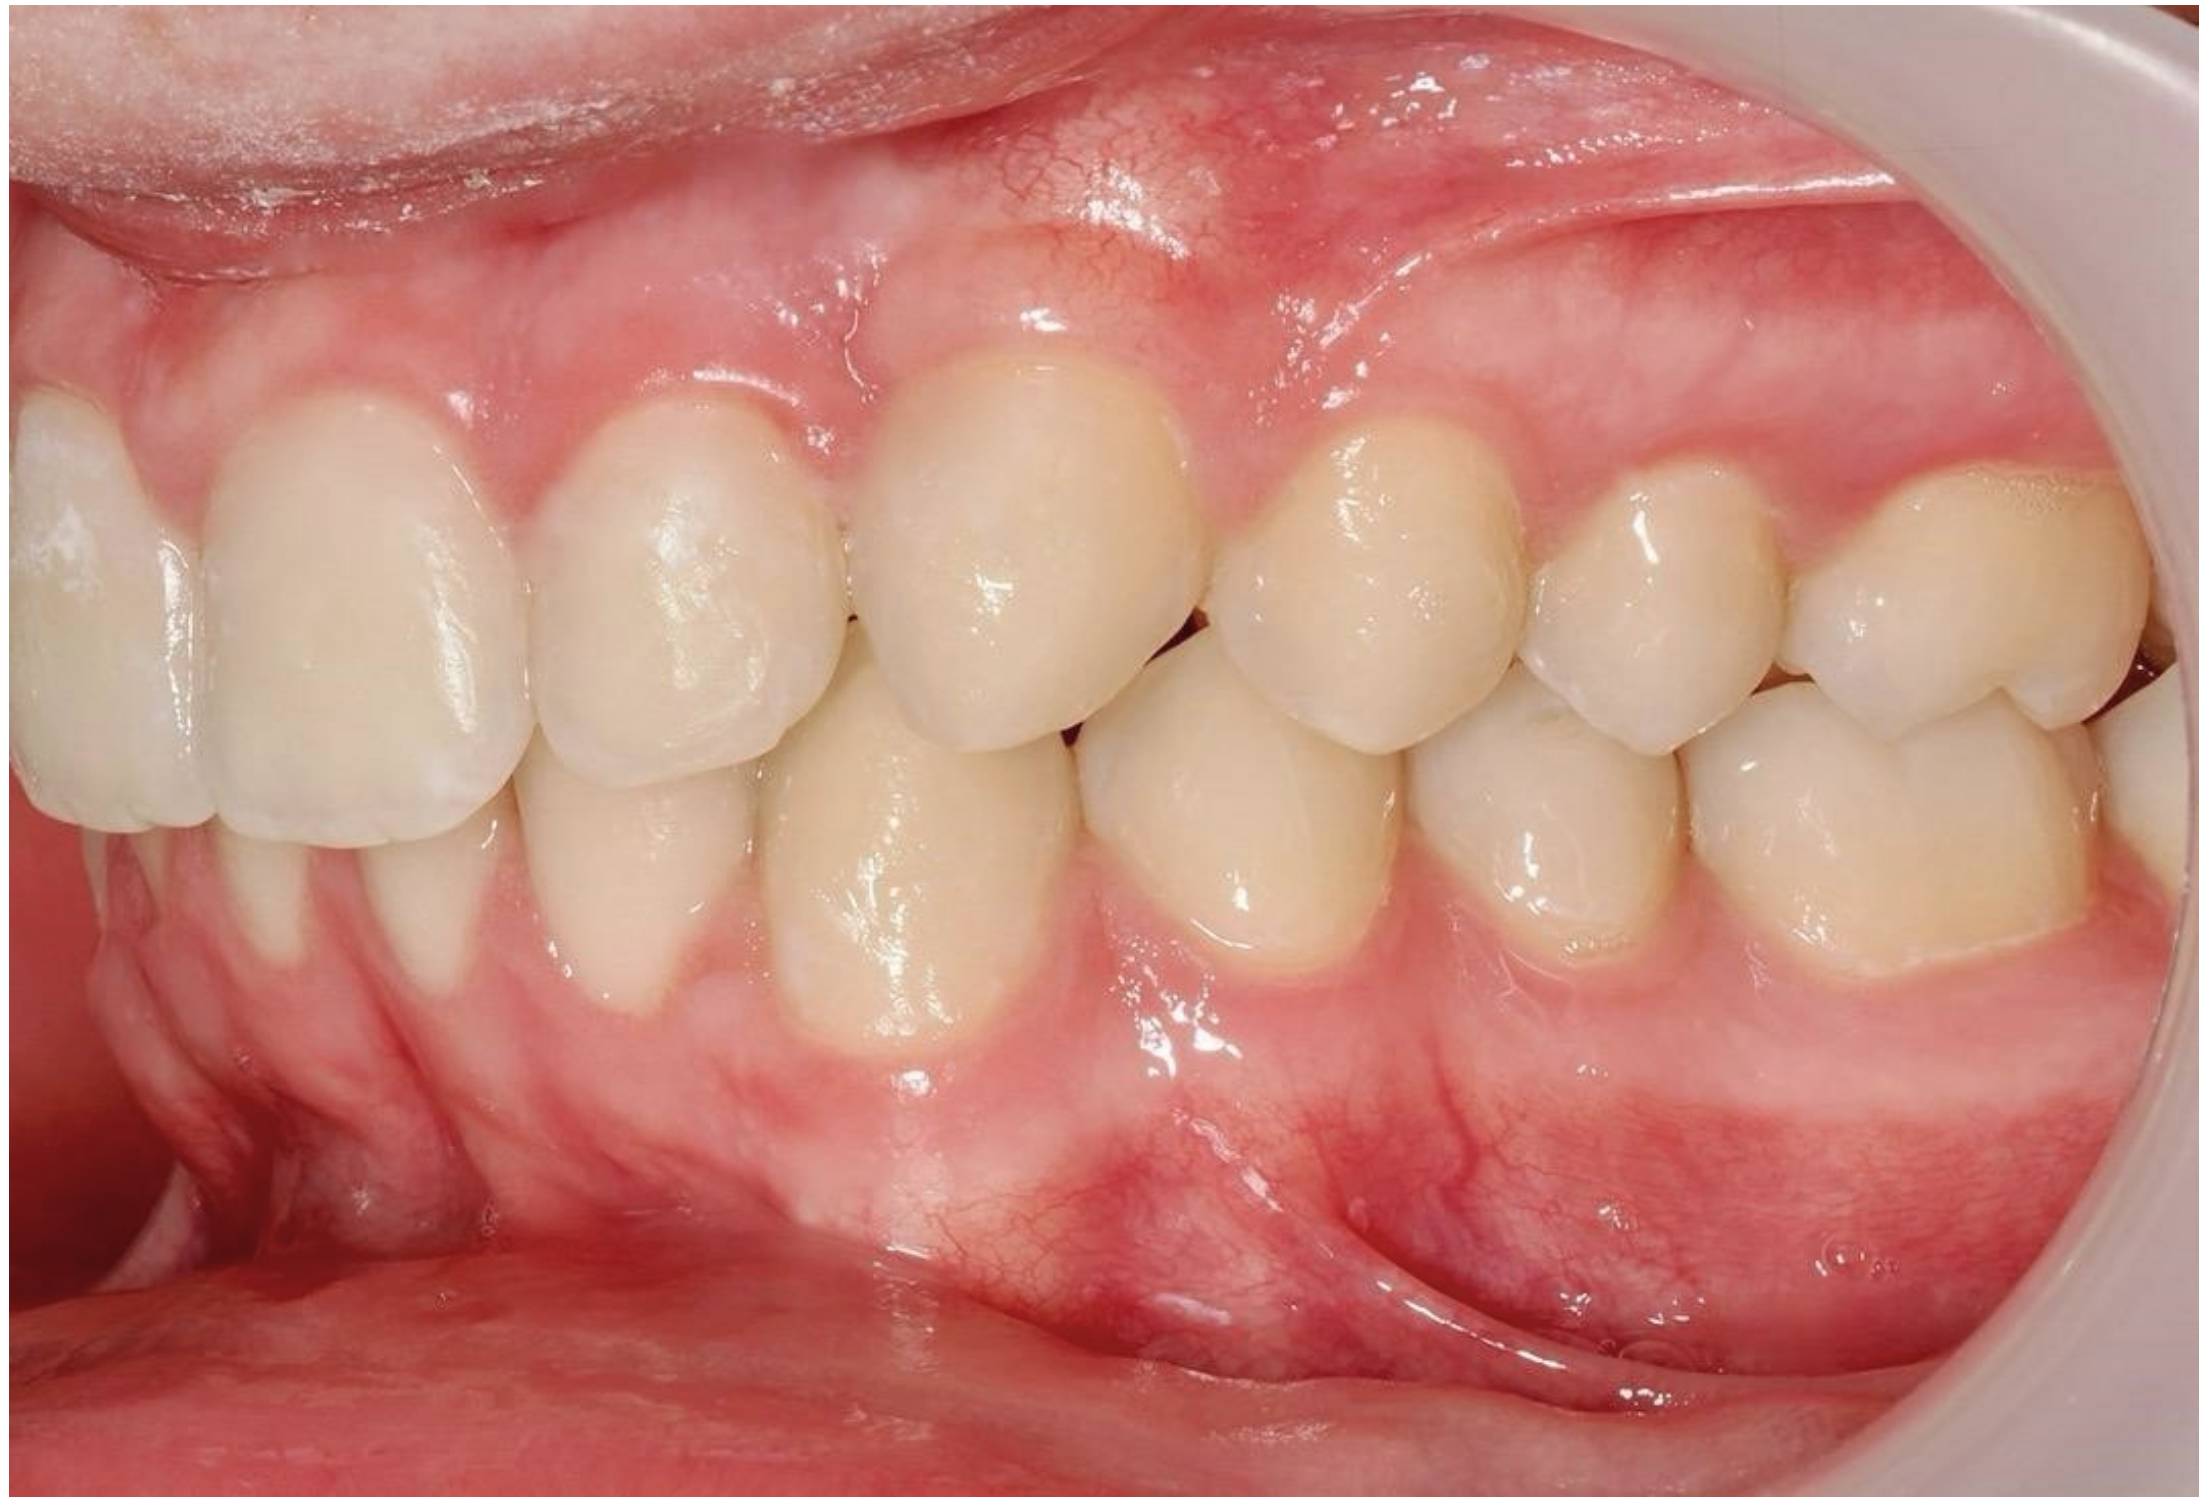

Ultimately, after 30 months of treatment, canine 23 was successfully repositioned into the dental arch, achieving functional occlusion (Figure 23).

Figure 23.

Canine 23 properly positioned in the arch in occlusion; 30 months of treatment.